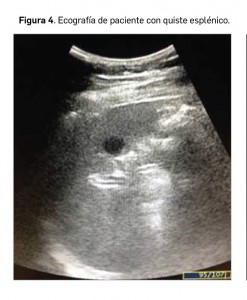

En ecografía (Figura 4), la apariencia es la típica de las lesiones quísticas, es decir, lesiones bien delimitadas, de contornos lisos y contenido líquido, siendo más frecuente la presencia de septos o tabiques en los quistes congénitos, a la par que es más frecuente la presencia de calcificaciones en los seudoquistes o quistes adquiridos. Otro tipo de lesiones quísticas en el bazo son menos frecuentes, destacando entre ellas el linfangioma quístico, que se caracteriza por la presencia de múltiples lesiones con morfología “en panal de abeja”.